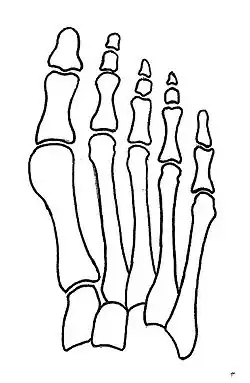

Normal foot skeleton

Fig 1a: Normal foot skeleton

Primus varus deformity is the leaning of the first metatarsal bone away from the second metatarsal and towards the opposite foot (Fig. 1). As it leans over, its head sticks out to form the bunion bump and it also widens the forefoot to cause shoes feeling too tight. Thus when bunion pain becomes unmanageable, surgical correction is to narrow the forefoot by repositioning of the first metatarsal head back to its normal position. This can be done by osteotomy (bone-breaking), soft tissue (non-osteotomy) or fusion techniques.